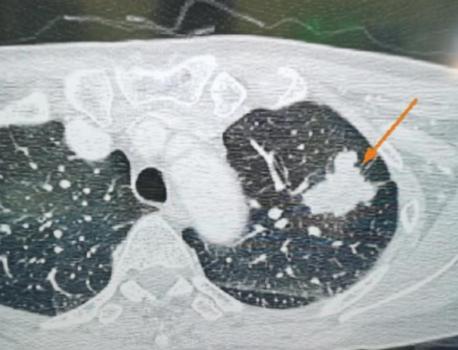

昨天发的小叔子腹膜后脂肪肉瘤做第四次手术时,被医生告知不能割了,瘤子太多太大已经无从下手了,动刀根本下不来手术台。很多友友说我在瞎说,[黑线]说哪个医院不得给做做ct看看有没有瘤子,说的还特别难听[泪奔],谁家能拿自家亲人的命来胡说瞎说!我小叔子每次去做手术肚子大的和带三个孩子的孕妇一样大,还用做啥检查,这最基本的常识谁能不知道?我们去301不是去治病,就是直接割瘤子,中国最厉害的刀高的大夫在301医院,割掉瘤子让人舒服一点是当务之急,也是唯一能做的!所以根本就不需要做任何检查。每次做完手术都挺了一年多肚子就撑不住了,最后这次大夫割开没想到瘤子比前几次长的都大都多,而且很多都长在器官上,无从下手,有的器官被挤的已经面目全非,大夫说下不来手术台了![流泪]